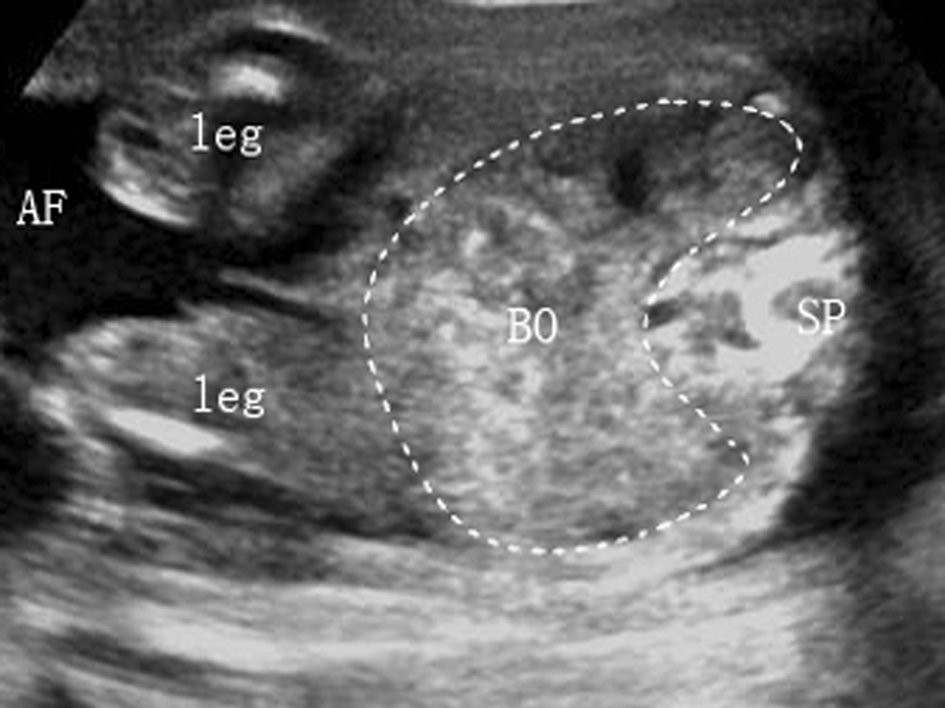

4.肠道 中期妊娠时肠道呈管壁回声略强、内含小暗区的蜂窝状结构(图4 BO),当肠道回声近似或强于脊柱回声时应进追踪观察,若同时出现羊水过多或肠管扩张等情况时,病理意义更大。

中晚期妊娠时,小肠位于下腹中央,结肠位于其周边、胎胃的下方,为无回声管状结构,可识别结肠带,在分娩前几周因胎粪充盈显示更佳。若以上正常位置关系发生了改变,则要仔细分辨是否存在腹壁缺损、脐疝或膈疝。不要把腹腔外的肠管误作外生殖器。

图4胎儿肠道横切面声像图